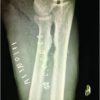

Case 1, A 7-year-old female child presented elsewhere with a history of a gradually growing swelling in her right arm for the past 2 years and an inability to flex the elbow. A small intervention was performed at the same site elsewhere 3 years ago but there were no records of details. She had no similar swellings elsewhere in her body, constitutional symptoms, or positive family history. On examination, a diffuse swelling was present over the Postero-lateral aspect of the right arm. It was approximately 7 × 6 cm in size, not fixed to the bone, non-fluctuant, firm in consistency, and the skin overlying the mass was pinchable with no distended veins. The elbow was completely stiff and only an abduction of 90° at the shoulder (Fig. 1). Radiographs of the arm and shoulder region showed no bony abnormality and only a thought-provoking soft tissue shadow in the middle third – proximal third junction of the humerus. Blood investigations ruled out infection. Magnetic resonance imaging (MRI) showed a large, soft tissue heterogeneous (T1 and T2) signal intensity mass, involving the triceps, extending up to the humerus but not infiltrating it (Fig. 2). An open biopsy of the mass done confirmed the diagnosis of desmoid fibromatosis (DF) by exhibiting proliferation of fibroblasts and collagen fibers characteristic of this condition. She underwent wide excision of the mass with the help of the onco-surgery team through posterior approach to humerus with a 15 cm long incision, enclosing biopsy scar. Intraoperatively, excision of the mass was achieved by dissecting the fibrosed triceps, mapping, and neurolysis of the entrapped radial nerve and hemostasis with electrocautery (Fig. 3). No intraoperative neuromonitoring or tourniquet was needed. The mass was retrieved in toto, margins were well circumscribed, hence no chemotherapy or radiotherapy was given. The child was immobilized with a POP cast in elbow flexion of 90° for 3 weeks. Gradual, active, and passive physiotherapy was done. Extension was achieved by gravity since more than 2/3 of the triceps mass was lost. At 2 years after index surgery, the child had gained near normal elbow range of movements and full abduction of the shoulder (Fig. 4) and was able to do activities of daily living, independently. Case 2, 8-month-old child presented with a slow-growing tumor of the right neck causing a severe torticollis deformity (Fig. 5a and b). Parents were advised physiotherapy and also had a steroid injection intramuscularly elsewhere, which showed no improvement. On examination, a large, firm swelling along the entire length of the sternocleido mastoid muscle was causing severe restriction of movements of the neck. Bony abnormalities were ruled out with X-ray; MRI done revealed DF, juxta internal jugular vein. The tumor was excised with musculoskeletal oncology and head–neck faciomaxillary surgical team and a cervical to chest pop was given for 6 weeks followed by a distraction collar for 3 months. No nerve damage occurred intraoperatively as careful dissection was done in the anterior and posterior triangles of neck and brachial plexus, subclavian artery was visualized and kept out of harm’s way (Fig. 6). Macroscopically it was a grey-white mass with no area of necrotic tissue (Fig. 7) and the histology showed proliferation of fibroblasts and collagen fibers (Fig. 8) characteristic of this condition. The child received no chemotherapy and as the tumor was excised in toto. The child was followed till 18 months postoperatively on a collar, hada mild residual tilt but the parents were satisfied with the clinical outcome.